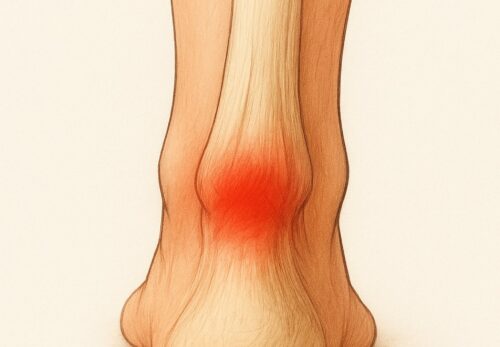

膝のお皿(膝蓋骨)のすぐ下、スネの骨(脛骨)にある

出っ張り部分が強く引っ張られることで炎症が起こり、

膝の下が腫れて痛みを感じます。特に走る・跳ぶ動作を

特に太ももの前の筋肉(大腿四頭筋)が硬くなると、膝の下にある脛骨粗面が強く引っ張られ、炎症や痛みの原因になります。

- 炎症による膝周囲の痛みをやわらげる

- 硬くなった大腿四頭筋やふくらはぎを緩めて、膝への負担を減らす

- 血流を改善し、回復を促す